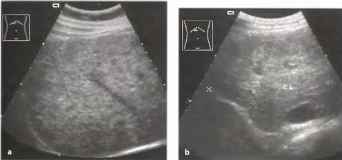

Как выглядит доля Риделя на УЗИ печени